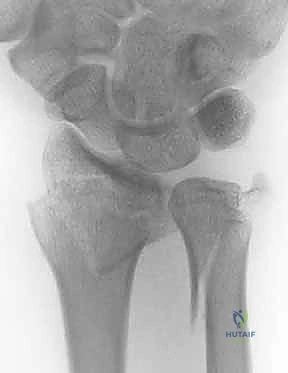

2. كسور رأس الزند (Ulnar Head Fractures)

رأس الزند هو الجزء المفصلي الدائري الذي يدور حوله الكعبرة.

* كسور مفصلية (Articular Fractures): تمتد خطوط الكسر لتشمل الغضروف المفصلي. إذا لم يتم إعادة العظام إلى وضعها التشريحي المثالي (Anatomic Reduction)، فإن المريض سيكون عرضة للإصابة بخشونة المفاصل المبكرة (Post-traumatic Osteoarthritis) وفقدان القدرة على تدوير الساعد.

1. الأشعة السينية (X-rays): بوضعيات متعددة (أمامية خلفية، وجانبية دقيقة). الوضعية الجانبية الحقيقية (True Lateral) حاسمة لاكتشاف أي خلع جزئي في المفصل (DRUJ).

2. الأشعة المقطعية ثلاثية الأبعاد (3D CT Scan): تُستخدم في الكسور المفتتة أو كسور رأس الزند المفصلية المعقدة، حيث تعطي خريطة دقيقة للجراح قبل الدخول لغرفة العمليات.